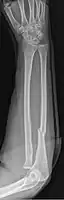

Monteggia fracture (type of ulna fracture)

Monteggia fracture (fracture of proximal ulna)

- Monteggia fracture - a fracture of the near to elbow end of the ulna with the dislocation of the head of the radius at the elbow joint.[3]